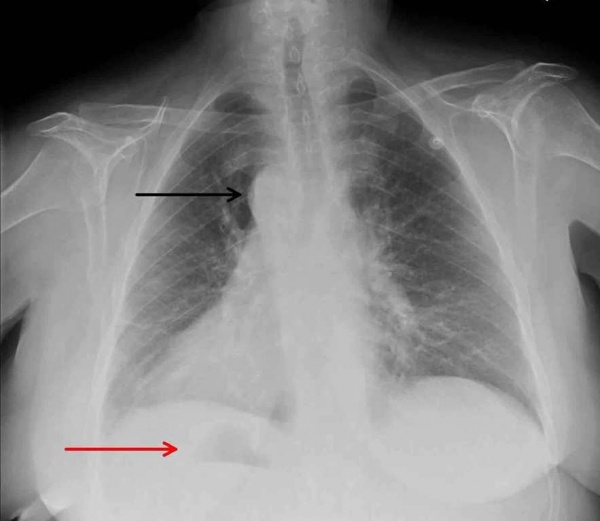

Q24.0 Декстрокардия